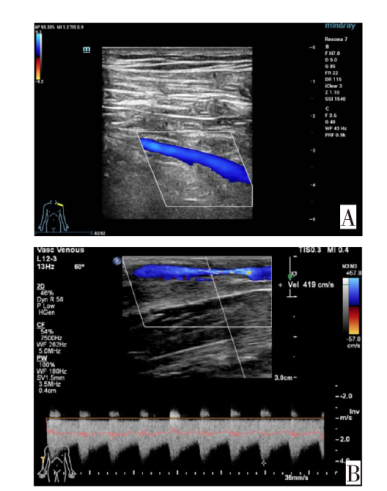

赵蕊, 张东亮, 贾建文, 等. 彩色多普勒超声评价血液透析患者自体动静脉内瘘的应用价值[J]. 中国超声医学杂志, 2017, 33(10):930-932.

ZHAO R, ZHANG D L, JIA J W, et al. Application of color Doppler ultrasound for arteriovenous fistula in hemodialysis[J]. Chin J Ultra Med, 2017, 33(10):930-932. doi:10.3969/j.issn.1002-0101.2017.10.022.